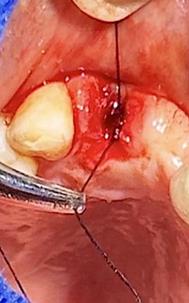

Sindesmotomía con un periostótomo de molt # 9, posteriormente se realizó la luxación con un elevador recto, buscando el punto de apoyo, seguido se efectuó la prensión con el fórceps 150 en el diente con sumo cuidado de no tocar la encía colocándolo hasta el cuello dental, haciendo movimientos de lateralidad y rotación hasta lograr la dilatación del alveolo, y finalmente la tracción del órgano dentario, observando que la raíz este integra, y que estructuras alrededor estén conservadas, de la misma forma se revisó el alveolo en busca de la presencia de granulomas o espículas óseas, una vez ya revisado se procedió al curetaje, con una cucharilla de lucas, se introdujo y se dio paso al retiro del exudado purulento, se realizó irrigación del alveolo con solución fisiológica, una vez limpio se realizó una sutura simple con sutura nylon, seda # 3/0 en el medio del alveolo con la finalidad de aproximar rebordes, evitar su contaminación por el ingreso de comida, además generar una mejor cicatrización en una zona estética , finalmente se aplicó presión por medio de una gasa que mordió el paciente por un lapso de 30 minutos, para contribuir con una hemostasia adecuada.

Figura 6. Sindesmotomía, luxación y prensión del incisivo lateral superior derecho pieza N.º 1.2

Elaboración: Los autores.